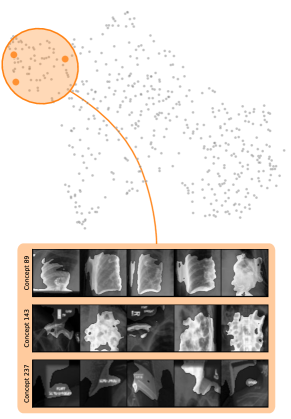

In contrast to detecting spurious samples, recent work focuses on identifying spurious model internals directly. This aligns with mechanistic interpretability, which seeks to decipher the internal mechanics of DNNs [56, 31, 13]. As outlined in Sec. 3.1, various global XAIs methods aim to explain the role of individual neurons, and these insights can be leveraged to detect spurious model internals by clustering learned concepts and identifying outliers. Given input data with samples, Pahde et al. [59] compute spatially aggregated relevances . Subsequently, they compute the pairwise cosine distance per column (i.e., channel/concept) and embed the resulting distance matrix in a low-dimensional space using dimension reduction techniques like t-Distributed Stochastic Neighbor Embedding (t-SNE) [71] or Uniform Manifold Approximation and Projection (UMAP) [49]. This low-dimensional embedding can be visualized to identify outliers through human inspection or anomaly detection algorithms, such as the Local Outlier Factor [12]. In summary, outlier representations can be identified in an embedding representation , obtained as

where reduces the dimension to , and the pairwise distance function is applied along all channel dimensions in the latent representation , either given by activations or relevance scores for layer . Note that this approach assumes over-parameterization resulting in redundant neurons, allowing to distinguish between similar and dissimilar concept representations. An example is shown in Fig. 4 (bottom), where latent relevance scores from a ResNet50 model trained for melanoma detection are used to identify outlier concepts, specifically a cluster focusing on band-aids rather than clinically relevant features. Notably, Eq. 3 can easily be extended to find outlier directions instead of neurons. Specifically, this involves a linear transformation of latent representations using the directions of interest, e.g., obtained in unsupervised manner as described in Sec. 3.1.

Similarly, DORA embeds a pairwise distance matrix of neuron representations into 2D, but proposes a data-agnostic approach and a tailored distance function [16]. Specifically, they generate ActMax samples as concept representation for neurons, referred to as natural Activation-Maximization signals (n-AMS). Each neuron is represented by a representation activation vector , measuring how much other neurons activate on the given n-AMS, and compute pairwise distances between the vectors. The resulting distance matrix is embedded into lower dimension to identify outlier representations. Notably, instead of generating ActMax samples, this approach can also be applied on real samples from a reference dataset.

Next, we apply bias identification approaches from the model perspective by identifying outlier neurons based on activation pattern via DORA and relevance pattern by clustering pair-wise cosine distances between concept relevance scores. We focus on latent activations and relevances after the third residual block. DORA uses a distance function based on how neurons activate upon each others n-AMS, achieving high similarity when neurons activate upon similar input signal. A 2D visualization of the resulting distance matrix is shown in Fig. 6 (bottom left). Identified outlier concepts include ruler () and (white) hair (). We further compute pairwise cosine distances between latent relevance scores , aggregated over spatial dimensions, and apply UMAP to embed the resulting distance matrix in . This results in high similarity between neurons (concepts) that the model uses similarly for predictions. The concept clustering is visualized in Fig. 6 (bottom right), highlighting two outlier clusters focused on rulers () and blueish tint ().

Results for other classes, model architectures, and datasets are presented in Appendix A.6.1. This includes experiments with ECG data in Fig. 10, revealing the artificially inserted static noise in the attacked lead from both data and model perspectives. Notably, dominant spurious concepts, such as the artificial timestamp in HyperKvasir or the static noise in PTB-XL, may not be detected as outlier concepts. In such cases, analyzing prediction sub-strategies via PCX may provide additional insights on spurious inlier behavior. Hard-to-interpret concept representations pose another challenge for the model perspective. For example, the brightness artifact in CheXpert is not clearly visible in the concept UMAP (see. Fig. 15, right), but can easily be detected using SpRAy (Fig. 15, left) or PCX (Fig. 22). In summary, while all considered spurious features are detected, the choice of bias identification approach is crucial, as some shortcuts are easier to detect as outlier concept (e.g., ruler) and others via PCX (e.g., brightness, static noise in ECG).